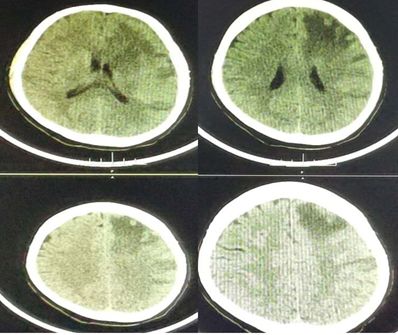

答案:化脓性脑室炎

补充图片,DWI也证实T2、FLAIR上四脑室、侧脑室似有液平的地方,是积脓。

绿色无坑,充分体现一个临床病例的特点,急性起病,发烧,神经功能缺损。影像上脑室增大,T2、FLAIR上四脑室似有积脓,室管膜高信号。很多人都猜对了。